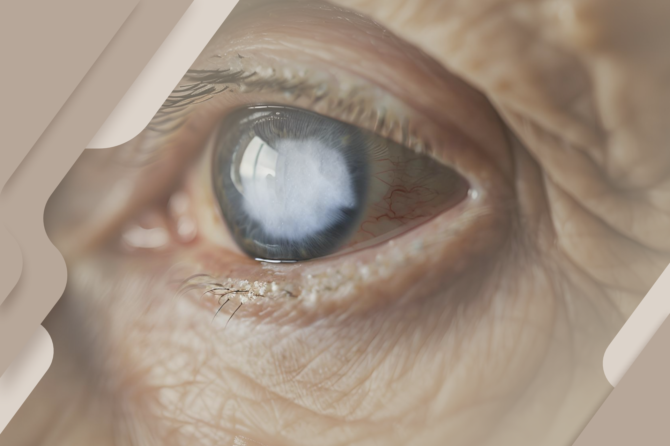

A catarata é uma condição ocular caracterizada pela opacificação do cristalino, a lente natural do olho responsável por focalizar a luz na retina. Quando o cristalino perde sua transparência, a visão se torna progressivamente embaçada, opaca ou amarelada, como se a pessoa estivesse olhando através de um vidro fosco.

A causa mais comum da catarata é o envelhecimento natural, sendo chamada de catarata senil. Com o passar dos anos, as proteínas do cristalino sofrem alterações que levam à perda de transparência.